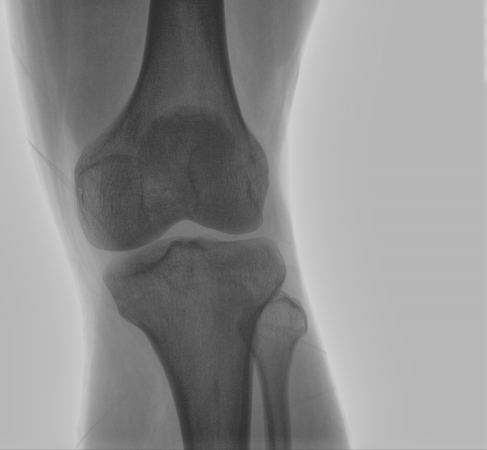

配備了兩種平板尺寸,大尺寸動(dòng)態(tài)平板探測(cè)器成像面積較傳統(tǒng)平板探測(cè)器提升了25%以上,在視野需求大的手術(shù)中,便于醫(yī)生更好定位病灶點(diǎn),規(guī)劃手術(shù)方案,減少因視野范圍不足而多次透視、點(diǎn)片造成的不便,不僅提高了手術(shù)效率,也減少了輻射劑量。